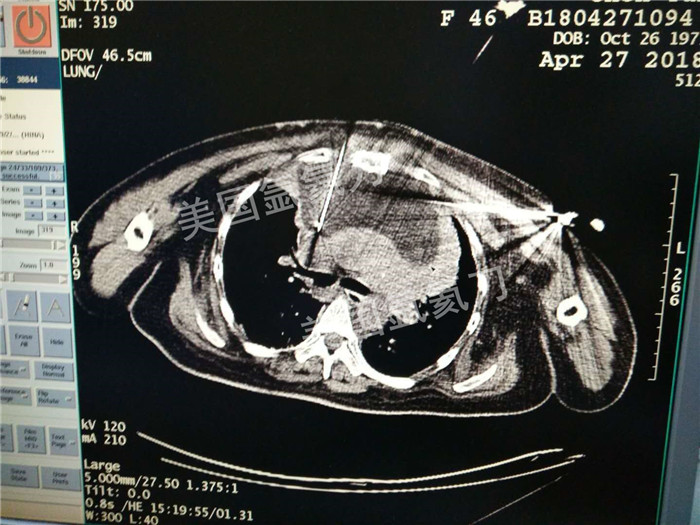

河北省中医院肿瘤科王利民主任胸腺19公分肿瘤氩氦刀手术

图片版权归美国氩氦刀所有,仅用于美国氩氦刀的宣传交流